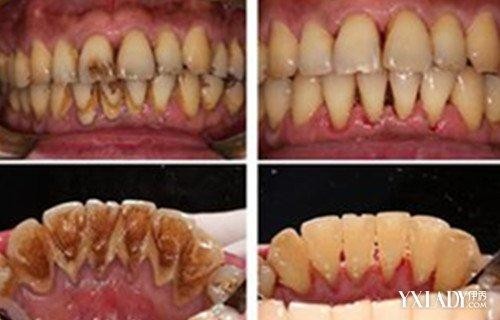

如果经常喝浓茶、咖啡等深色的食物,还有喜欢嚼槟榔(吃槟榔会增加口腔癌风险,建议早点戒掉)等情况都容易导致神色食物沉积在牙齿表面,从而出现黑点黑线。

如果是外源性的色素沉积导致的黑点黑线,可以考虑通过刷牙将其清理干净,如果刷牙也没办法清理干净的话,则可以通过超声波洁牙将这些顽固的外源性色素清理干净。

添加图片注释,不超过 140 字(可选)